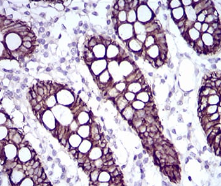

CDH17单克隆抗体[7D10E]

CDH17 Mouse Monoclonal antibody[7D10E]

Immunogen :   Purified recombinant fragment of human CDH17 (AA: extra(600-707)) expressed in E. Coli.

IHC    1/200 - 1/1000